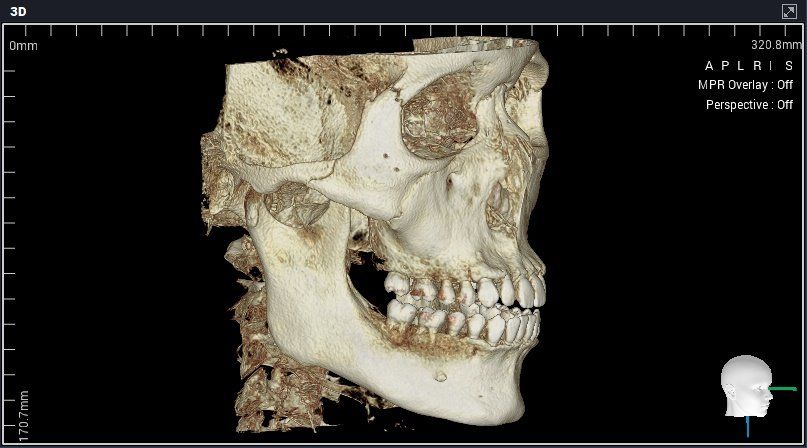

• 4번 째 사진

A치과는 평균남성보다 하관이 크고 조금 턱이 나와서 입이 전체적으로 나와보이는 거라서 구강악안면외과가서 양악이나 윤곽수술상담을 받아보라고 했습니다.

하악이 약간 돌출된것으로 보이나 무조건 수술을 해야하는 경우로 보이진 않습니다. 본인이 원하시는 것이 무엇인지를 결정하시는게 중요하겠습니다.

세가지 치과 모두 맞는 말입니다. 지금 보여주신 자료를 종합해보면 경미한 3급 부정교합입니다.

이 상태에서 교정도 가능하고 양악도 가능하지만 치료 이후 변화되는 모습에는 한계가 있습니다. 또한 부정교합 및 골격부조화가 심하지 않으므로 심미적으로 불편감이 없다면 3번 치과처럼 치료하지 않아도 됩니다. 물론 심미적으로 문제가 된다고 생각한다면 이때는 두가지 방법 모두 가능합니다.

다만 양악수술은 확실히 골격 부조화를 잡아줄 수 있다면 교정에는 한계가 있으니 전문가와 상담이 필요합니다.